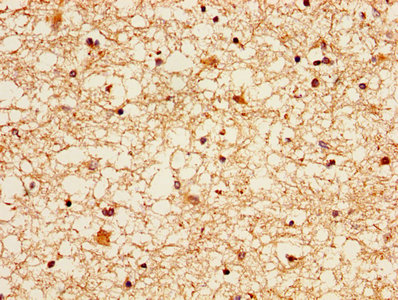

IHC image of CSB-PA02159A0Rb diluted at 1:300 and staining in paraffin-embedded human brain tissue performed on a Leica BondTM system. After dewaxing and hydration, antigen retrieval was mediated by high pressure in a citrate buffer (pH 6.0). Section was blocked with 10% normal goat serum 30min at RT. Then primary antibody (1% BSA) was incubated at 4°C overnight. The primary is detected by a biotinylated secondary antibody and visualized using an HRP conjugated SP system.